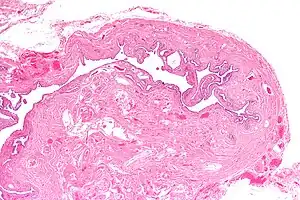

| Micrograph of salpingitis isthmica nodosa, showing the characteristic nodular thickening. H&E stain. | |

Salpingitis isthmica nodosa (SIN), also known as diverticulosis of the Fallopian tube, is nodular thickening of the narrow part of the uterine tube, due to inflammation.

It is characterized by nodular thickening of the tunica muscularis of the narrow (isthmic) portion of the Fallopian tube. In severe cases, it leads to complete obliteration of the tubal lumen. It is uncommonly bilateral.[2]